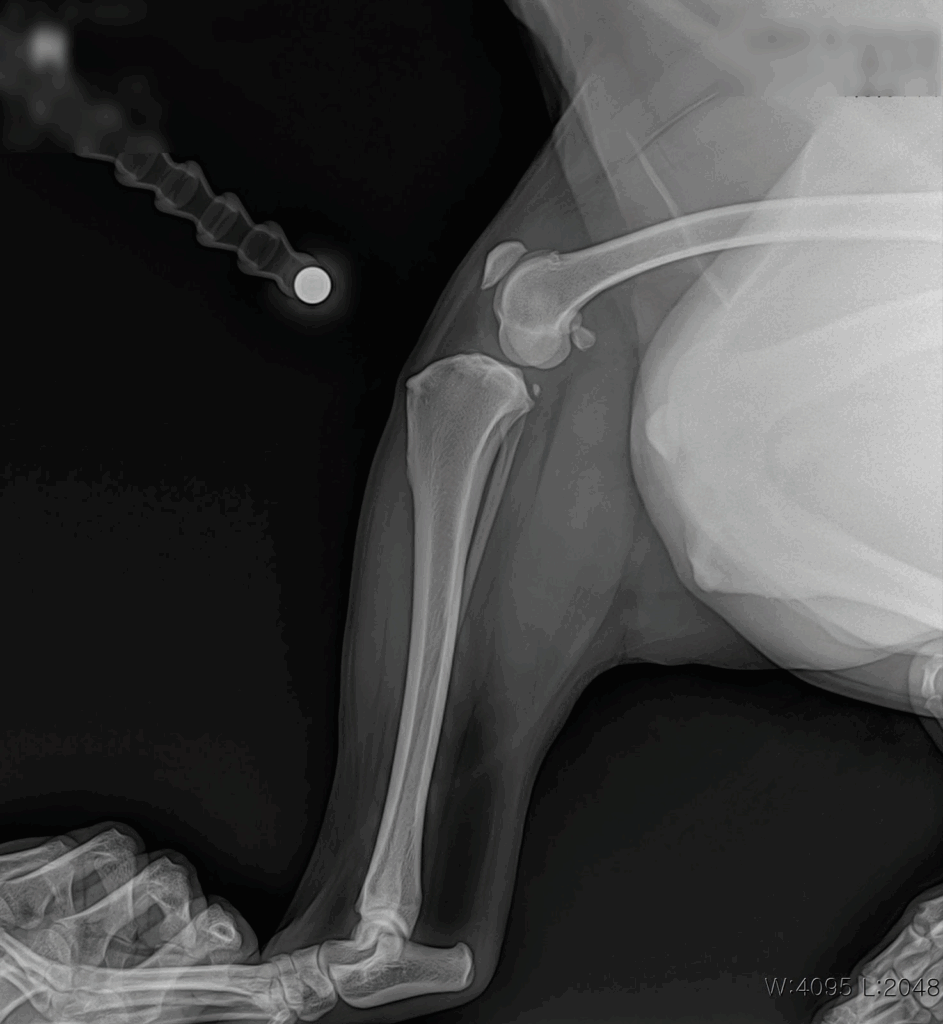

6살의 대형견 D는 며칠 전부터 오른쪽 뒷다리를 들고 절뚝이는 모습을 보이며 평소와는 다른 이상 행동을 보여 보호자님께서는 걱정된 마음으로 병원을 내원하셨습니다. D는 대형견으로 관절에 무리가 가기 쉬운 체형이었고, 내원 당시 우측 후지에 뚜렷한 파행이 관찰되었습니다. 정확한 진단을 위해 신체검사와 방사선검사를 진행하였습니다.

수술 전 방사선검사 사진 / 출처: 라온동물메디컬센터

신체검사와 방사선 검사를 통해 오른쪽 무릎의 전십자인대 단열이 진단되었습니다. 이는 보행에 큰 불편을 주는 상태로, 빠른 수술적 처치가 필요했습니다.